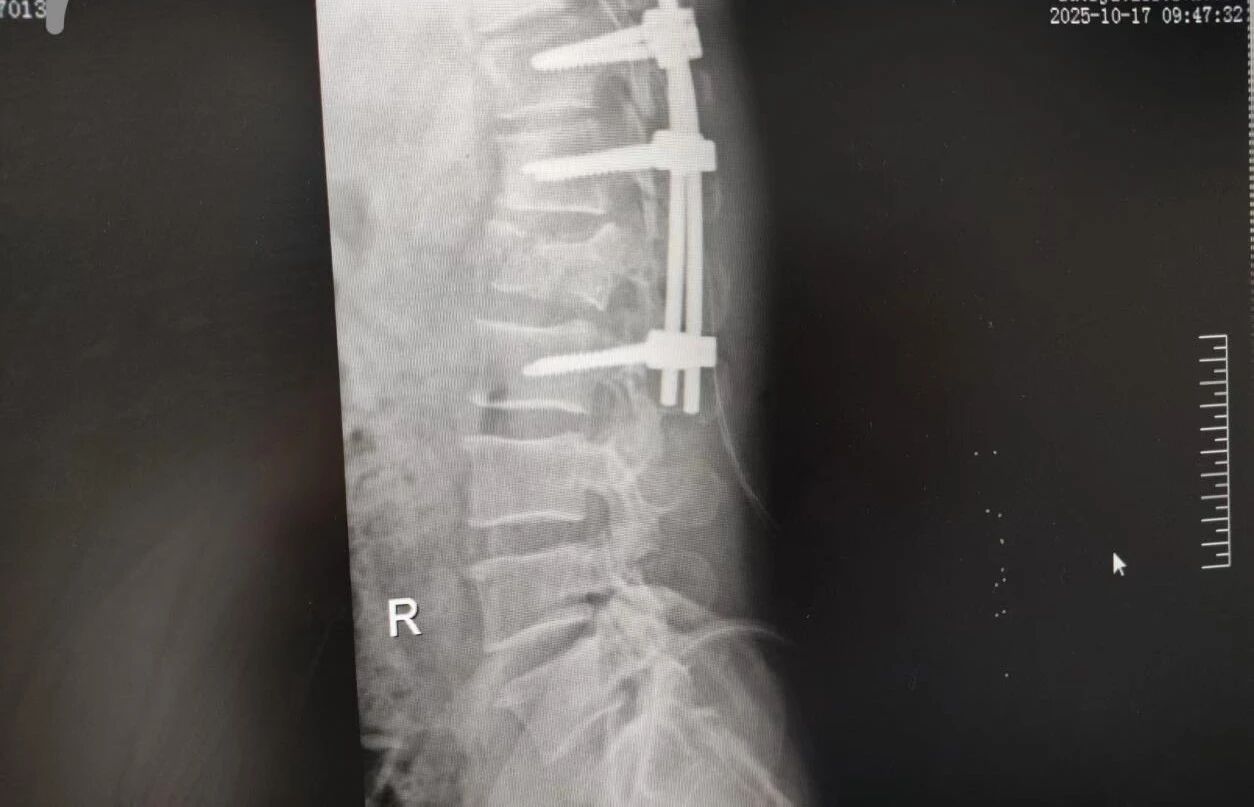

針對(duì)腰椎傷情,骨科竇志剛醫(yī)生團(tuán)隊(duì)緊急開展腰 1 椎體爆裂性骨折切開復(fù)位內(nèi)固定術(shù) + 椎板切除減壓術(shù)。手術(shù)室、麻醉科無(wú)縫銜接開通綠色通道,手術(shù)團(tuán)隊(duì)快速就位,術(shù)后患者下肢活動(dòng)恢復(fù)自如。